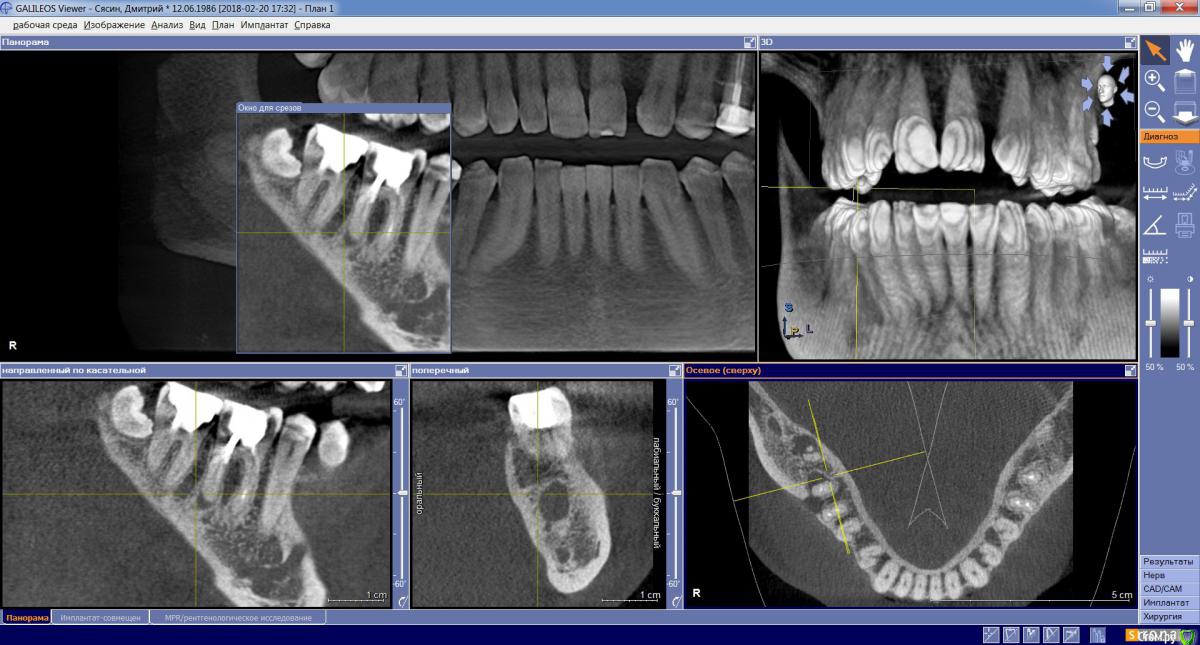

dims5 Опубликовано 21 февраля, 2018 Поделиться Опубликовано 21 февраля, 2018 Добрый день!Подскажите пожалуйста,если какая-либо надежда сохранить зубы 6-7? Зубы были пролечены несколько лет назад, не беспокоили длительное время и вот сейчас вылез свищ.Очень хочется сохранить зубы, а врач настаивает на удалении и постановке имплантов. Хотелось бы если есть хоть какая-то надежда попробовать из вылечить.Скриншоты сделал в разных нескольких разрезах чтобы лучше было видно состояние.Спасибо! Ссылка на комментарий

dims5 Опубликовано 21 февраля, 2018 Автор Поделиться Опубликовано 21 февраля, 2018 Если судить только по снимку, то вполне нормальные шансы на сохранение зубов 6 и 7.А вот 8 надо убирать Большое спасибо за мнение! А вы посмотрели на второй снимок(файл 1.jpg) на нем как раз видны размеры кист( воспаления) ? Ссылка на комментарий

DmitrySH Опубликовано 21 февраля, 2018 Поделиться Опубликовано 21 февраля, 2018 А вы посмотрели на второй снимок(файл 1.jpg) на нем как раз видны размеры кист( воспаления) ? Конечно, это не сильно принципиально Ссылка на комментарий